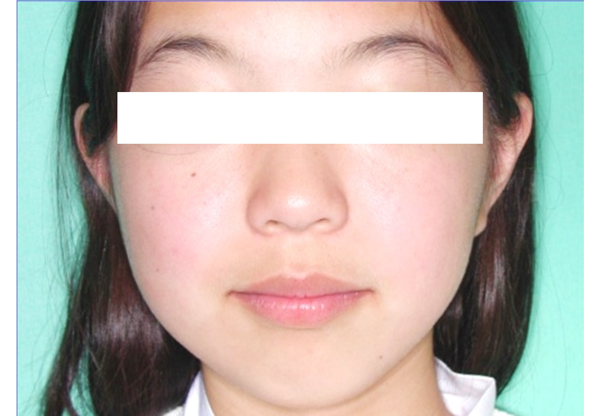

- 従来の矯正治療のみで十分な成果が得られた事例

-

【治療開始年齢】

【治療費用】約110万円(税別)

【総治療期間】約3年半

【患者さんの症状】この方は、一番奥の歯だけしか咬み合っておらず、外科的な矯正治療でしか治せないと考えておられました。できれば避けたいと考えて相談に来られました。過去の治療例をお見せして、相談して、協力が十分にして頂いた上でできるところまで矯正治療だけで治療しましょうということになりました。

【治療結果】開始すると十分な協力が得られて、矯正治療のみで十分な成果が得られました。